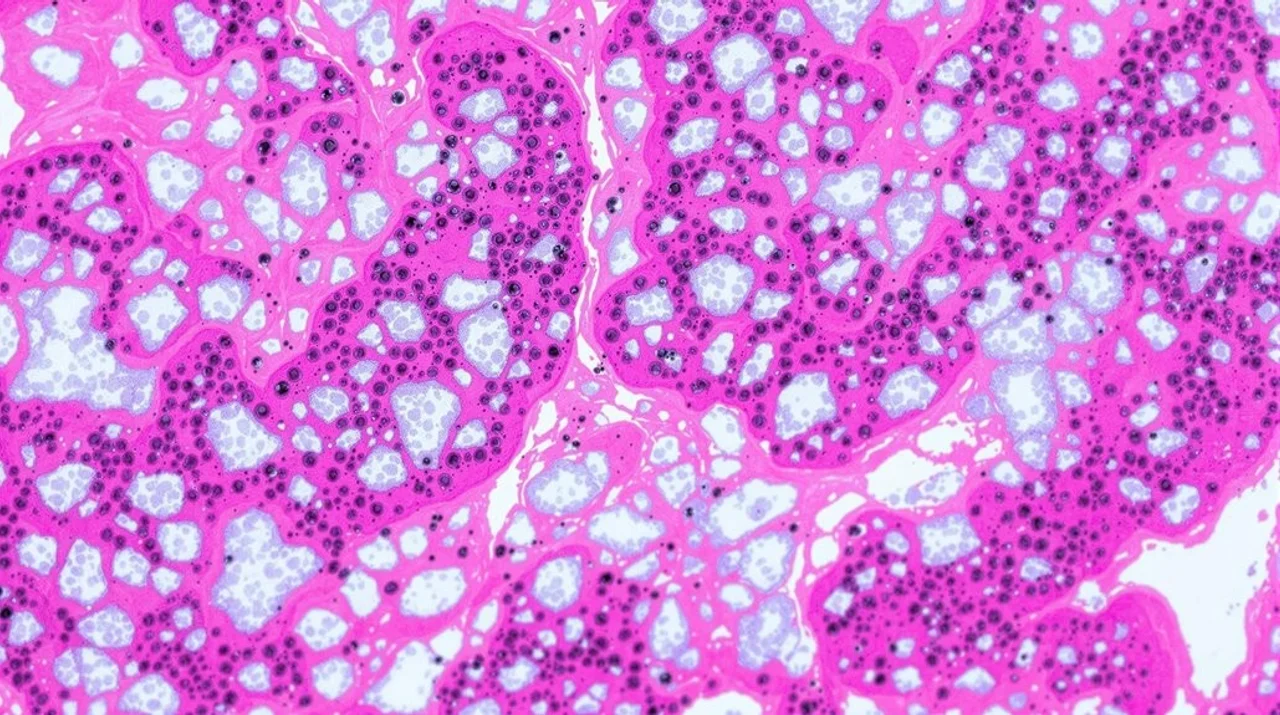

Although ACE inhibitors are commonly associated with coughing side effects, a rare but significant case report has documented eosinophilic interstitial lung disease (ILD) linked to metformin use. This notable case involved a 64-year-old male who developed respiratory symptoms during taking the diabetes medication, with his condition improving substantially after discontinuing metformin.

The diagnosis of metformin-induced eosinophilic ILD requires specific testing, including pulmonary function tests, high-resolution chest computed tomography, and bronchoscopy with bronchoalveolar lavage. These diagnostic tools help distinguish this rare complication from other respiratory conditions. The condition typically presents with progressive symptoms such as dyspnea, persistent cough, and fatigue, reflecting the underlying inflammation and scarring of lung tissue.